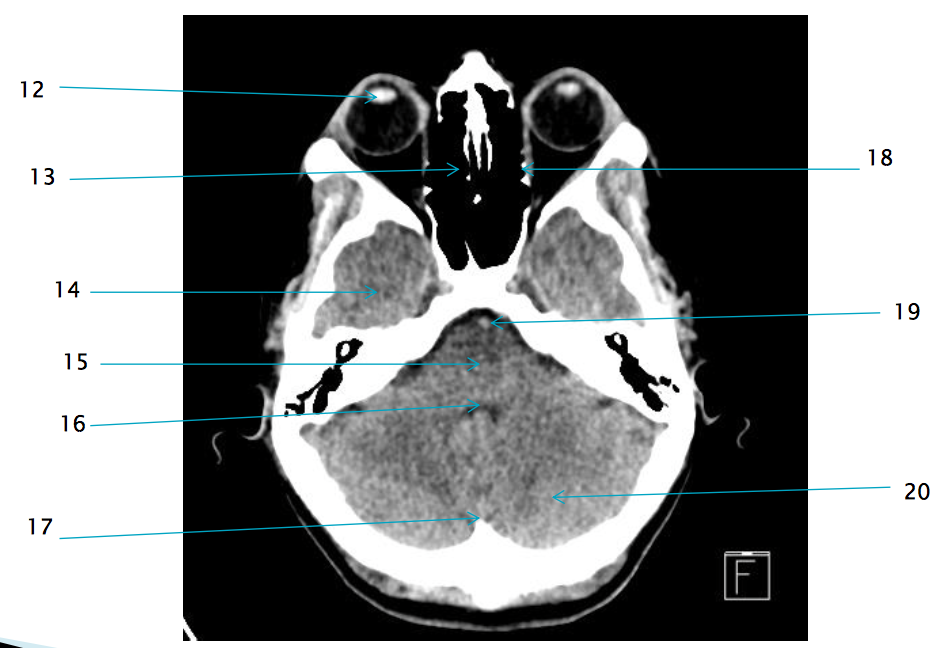

12

lens of R eye

13

ethmoid air cells R

14

R temporal lobe

17

internal occipital protuberance

19

basilar artery